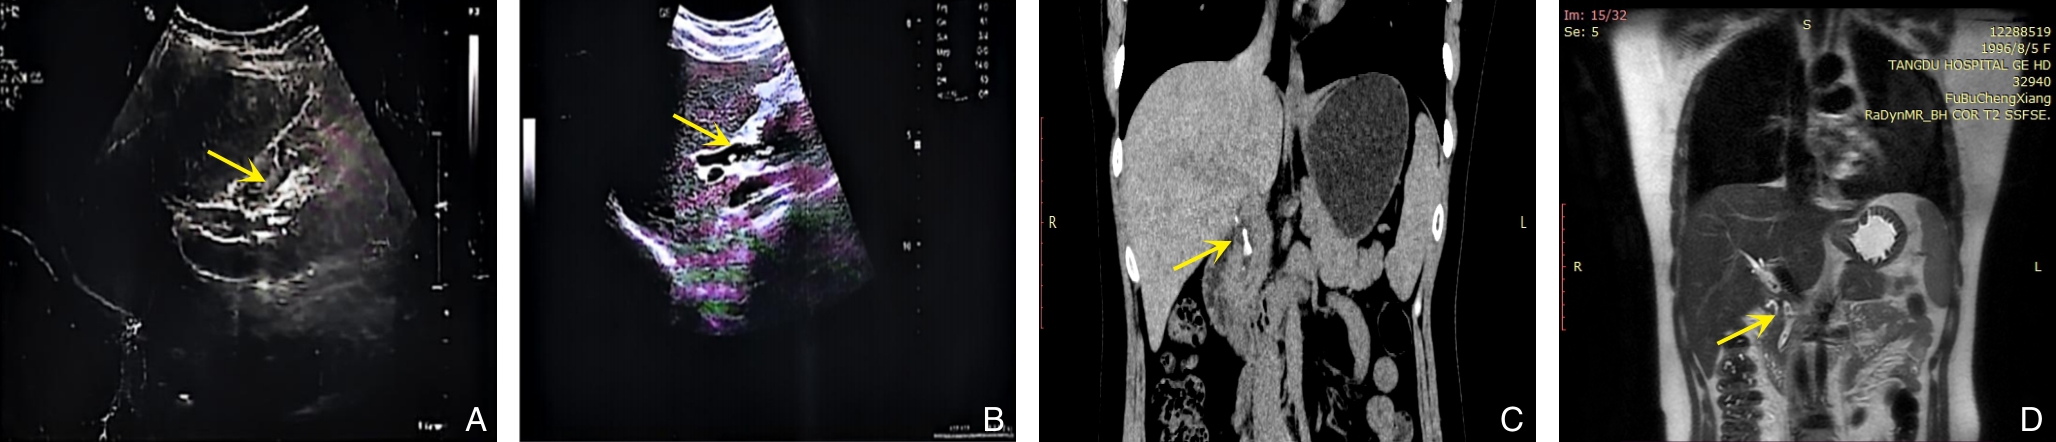

背景与目的 胆总管结石合并壶腹周围癌临床罕见,二者症状重叠,易导致误漏诊并延误治疗。本研究旨在分析其误漏诊特点、原因及优化诊断策略。方法 回顾性分析2022年11月—2025年8月河北医科大学第二医院普外一科收治的9例胆总管结石合并壶腹周围癌误漏诊患者的临床资料,重点总结首诊特征、影像学表现、确诊途径及治疗结局。结果 9例患者均以胆囊结石、胆总管结石为首诊诊断并接受相关治疗,误漏诊时间为35~180 d。初诊多依赖腹部超声及CT,均未发现壶腹部病变。转诊后经增强CT、经内镜逆行胰胆管造影活检或EUS-FNA明确诊断。7例行胰十二指肠切除术,2例行内镜胆道支架置入。随访5~30个月,3例死亡。误漏诊主要与临床表现重叠、对肿瘤警惕性不足、过度依赖常规影像检查及术中探查不充分有关。结论 胆总管结石合并壶腹周围癌易被掩盖,尤其在老年及伴胆管扩张、肿瘤标志物升高患者中应提高警惕。构建“影像筛查-内镜评估-病理确诊”的分层诊断路径,并规范术中探查与术后随访,有助于降低误漏诊率。